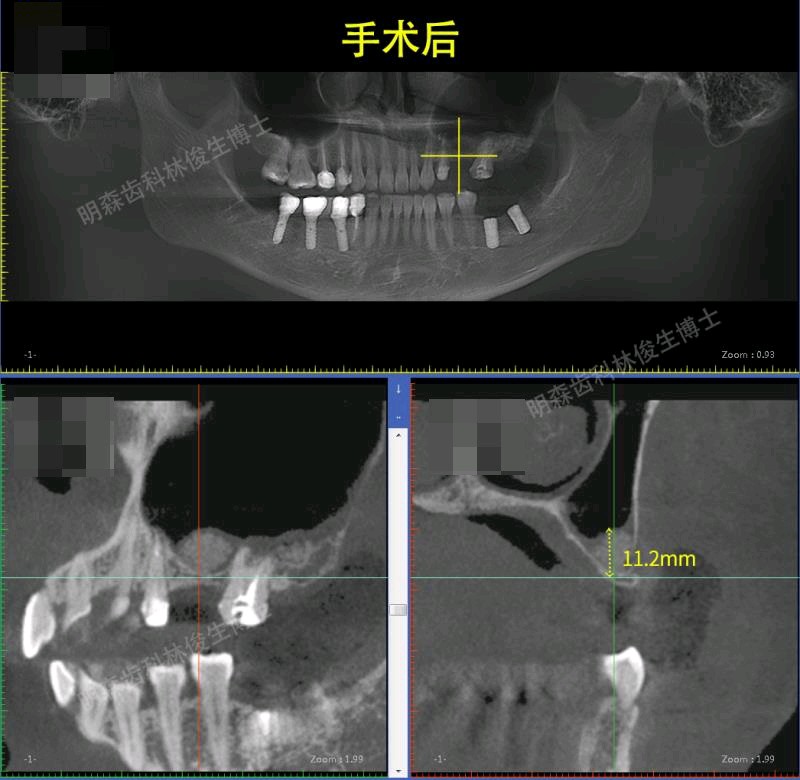

治疗方案:1.建议13-23贴面+14,15,33-43贴面修复,上前牙邻面龋补牙。 2.38.48拔除 3.24-26连冠修复,14.15换全瓷冠 4.25,27外提+植骨+种植,36,37种植修复(ITI钛锆)5.17充填治疗

此患者已跟踪近三年,一切情况良好。令我印象最深刻的是,刚种完25、27回家没多久,就微信我说没啥感觉,晚上能不能打球。。。。。看来对篮球是真的热爱啊,NBA没他,我不看。提醒大家,不管种牙后有没有不适感,都要好好休息,不要进行剧烈运动、不要熬夜,谨遵医嘱。